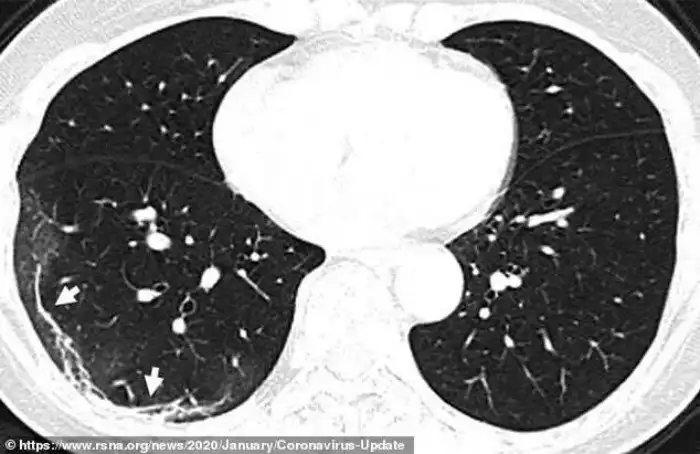

Рентгенограммы и томограммы легких 44-летнего китайского пациента, умершего от коронавируса, демонстрируют, как вирус разрушает легочную ткань. По утверждениям медиков, повреждения похожи на те, что обнаруживались в легких жертв атипичной пневмонии и ближневосточного респираторного синдрома.

Рентгеновские снимки и томограммы легких 44-летнего пациента, умершего от коронавируса, были представлены китайскими врачами. Они дают подробную картину того, как вирус разрушает легкие человека. На снимках видны белые пятна в нижних отделах легких. Медики называют их "субплевральными уплотнениями по типу матового стекла". В этих областях воздушные пузырьки легких частично заполнены содержимым. Похожие поражения наблюдались также у пациентов с атипичной пневмонией и ближневосточным респираторным синдромом.

Умерший 44-летний мужчина из Китая жил в Ухани и работал на местном рынке морепродуктов, который, вероятно, стал источником нового вируса. Он был госпитализирован 25 декабря 2019 года после двух недель болезни. Врачи диагностировали у него пневмонию и острый респираторный дистресс синдром. Несмотря на лечение, он умер неделю спустя. Субплевральные уплотнения видны в его легких очень отчетливо. На снимках видно, как легкие со временем, от снимка А до снимка F, все сильнее заполняются жидкостью. Компьютерная томограмма легких 54-летней женщины, подхватившей коронавирус во время поездки в Ухань, показывает схожую картину.